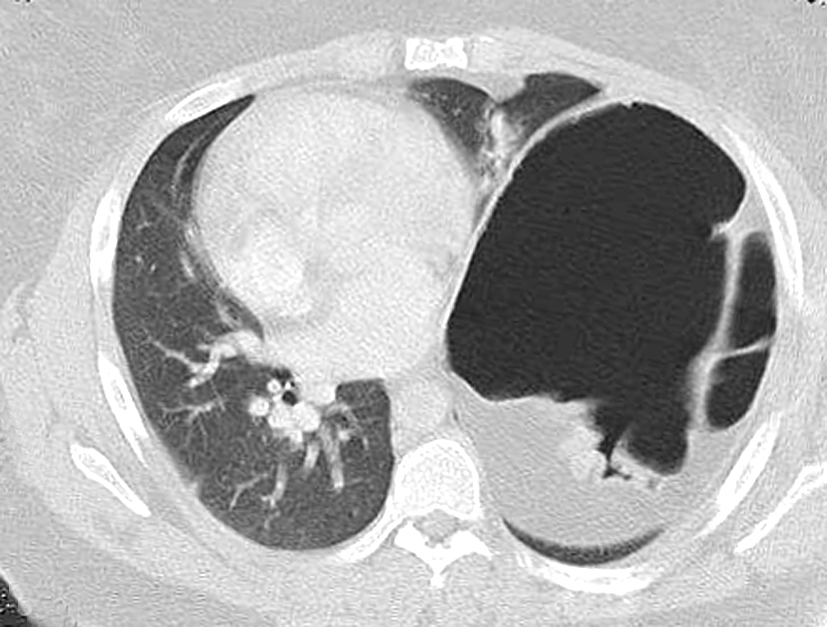

A congenital abnormality characterized by the elevation of the diaphragm dome. It is the result of a thinned diaphragmatic muscle and injured phrenic nerve, allowing the intra-abdominal viscera to push the diaphragm upward against the lung. A congenital or acquired abnormality characterized by elevation of the hemidiaphragm.

A congenital abnormality characterized by the elevation of the diaphragm dome. It is the result of a thinned diaphragmatic muscle and injured phrenic nerve, allowing the intra-abdominal viscera to push the diaphragm upward against the lung.

Diaphragmatic eventration (DE) is the abnormal elevation of a portion or entire hemidiaphragm due to a lack of muscle or nerve function while maintaining its anatomical attachments. The abnormality can be congenital or acquired, thus presenting in both the pediatric and adult populations.

Eventration of the diaphragm in infants is an uncommon disorder in which all or part of the diaphragmatic muscle is replaced by fibroelastic tissue, leading to a thinned and pliable central portion of the diaphragm. It is a result of either inadequate development (congenital) or atrophy (acquired) of the diaphragm.

Eventration of the diaphragm is a term used to describe an abnormal elevation of part or whole of the hemidiaphragm, where the whole or part of the diaphragm is made up of a thin fibro membranous sheet replacing normal diaphragmatic musculature.

It is a condition in which all or part of the diaphragm is largely composed of fibrous tissue with only a few or no interspersed muscle fibers. It can be complete or partial. Complete eventration of the right diaphragm, as seen in this adult patient, is relatively rare.

Raised hemidiaphragm The right hemi-diaphragm usually lies at a level slightly above the left. There are many possible causes of a raised hemidiaphragm such as damage to the phrenic nerve, lung disease causing volume loss, congenital causes such as a diaphragmatic hernia, or trauma to the diaphragm.

A congenital abnormality characterized by the elevation of the diaphragm dome. It is the result of a thinned diaphragmatic muscle and injured phrenic nerve, allowing the intra-abdominal viscera to push the diaphragm upward against the lung.